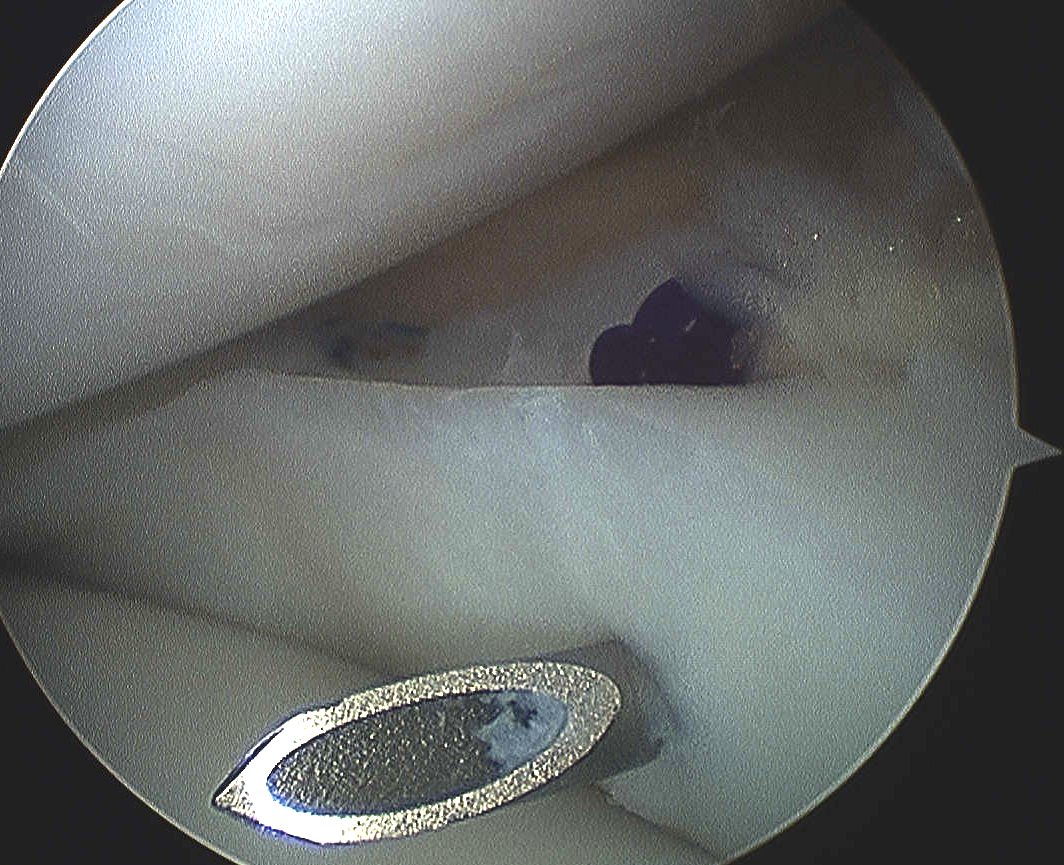

- with shaver / rasp

2. Trephine meniscocapsular periphery

- with spinal needle to promote vascular channels

2. Inside out

Technique

Require

- double armed sutures with long flexible needles

- use single or double cannula system

Make open posteromedial / posterolateral approach

- retrieve the sutures needles as they exit the joint capsule

- protects neurological structures (saphenous / CPN) from needle or suture injury

- sutures then tied over capsule

- pass in flexion to protect structures

Pass the needles about the tear

- vertical or horizontal mattress sutures

- absorbable or non absorbable 2.0 suture

- every 2-3 mm

Tie sutures over capsule

- tie in extension or will break when patient extends leg